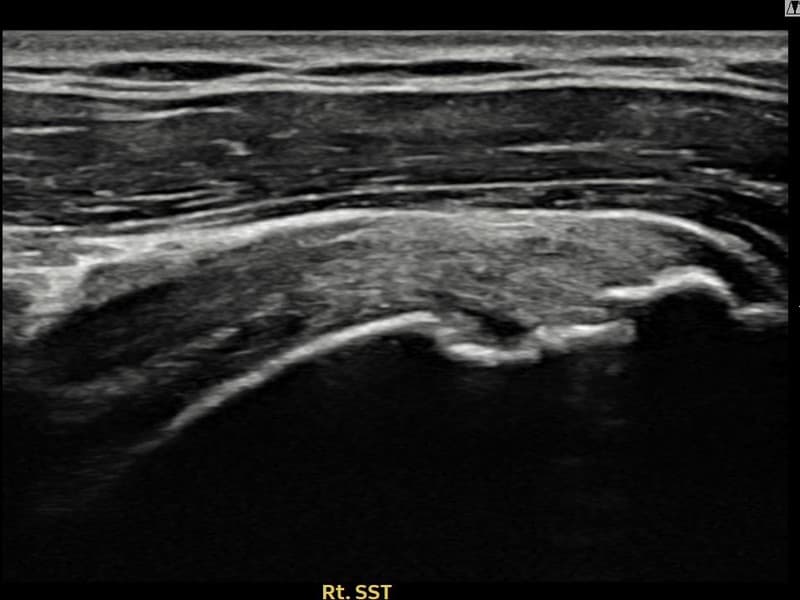

After

시술 전 초음파 측정 결과 파열 크기는 13mm × 6mm (힘줄 두께의 약 62% 결손)로 확인되었습니다. 시술 전 초음파에서 우측 극상근건 점액낭면측의 광범위한 에코 단절과 힘줄 두께의 현저한 감소가 확인되었습니다. 시술 후 초음파에서 점액낭면측 힘줄 경계가 선명해지고 연속성이 완전히 회복된 것이 관찰되었습니다.

40대 후반 남성 환자분으로, 골프를 즐겨 하시다 스윙 동작 중 어깨에 통증이 생겨 운동을 중단하셨습니다. 이후 통증이 악화되어 팔을 앞으로 뻗거나 위로 올리기도 어려운 상태가 되어 내원하셨습니다. 초음파 검사에서 우측 극상근건 점액낭면측의 광범위한 부분파열이 확인되었으며, 파열 두께와 범위를 고려하여 초음파 유도 하 축소봉합술을 시행하였습니다. 시술은 당일 귀가로 이루어졌으며, 이후 보조기 착용 6주 후 단계적으로 어깨 근력 강화 운동을 진행하였습니다. 시술 9주 후 추적 초음파에서 점액낭면측 힘줄 연속성이 완전히 회복된 것이 확인되어 골프 복귀에 성공하셨습니다.